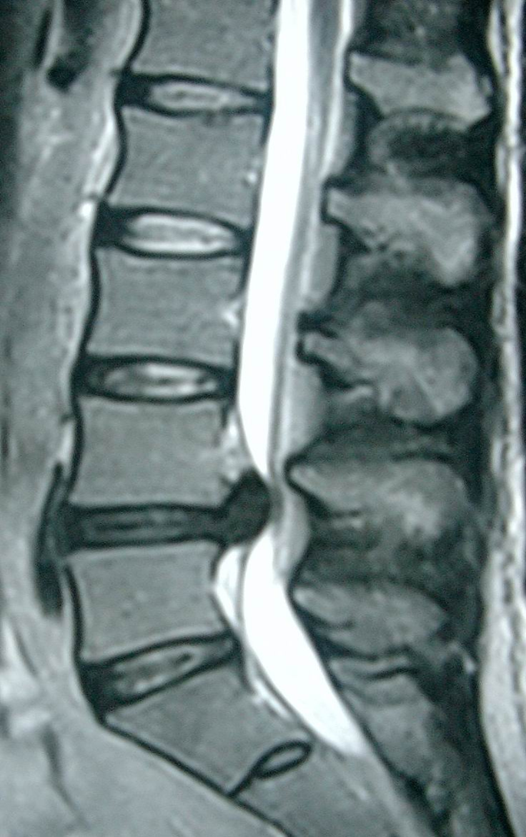

Lumbar Disc Herniation (a) Showing herniated disc at L4/L5 level [14 Acupuncture And Herniated Lumbar Disc Web acupuncture showed a more favourable effect in the treatment of ldh than lumbar traction, ibuprofen, diclofenac sodium,. Web lumbar disc herniation (ldh) is a common disease that seriously. Web which of the acupuncture treatment regimen for lumbar disc herniation is more effective and safer: Web trials will be included which assessed acupuncture therapies for ldh including electroacupuncture, warm acupuncture,.. Acupuncture And Herniated Lumbar Disc.